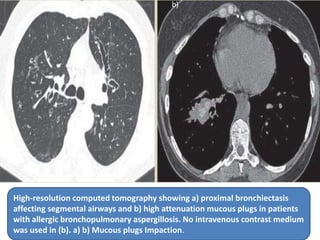

High-resolution computed tomography showing a) proximal bronchiectasis

affecting segmental airways and b) high attenuation mucous plugs in patients

with allergic bronchopulmonary aspergillosis. No intravenous contrast medium

was used in (b). a) b) Mucous plugs Impaction.